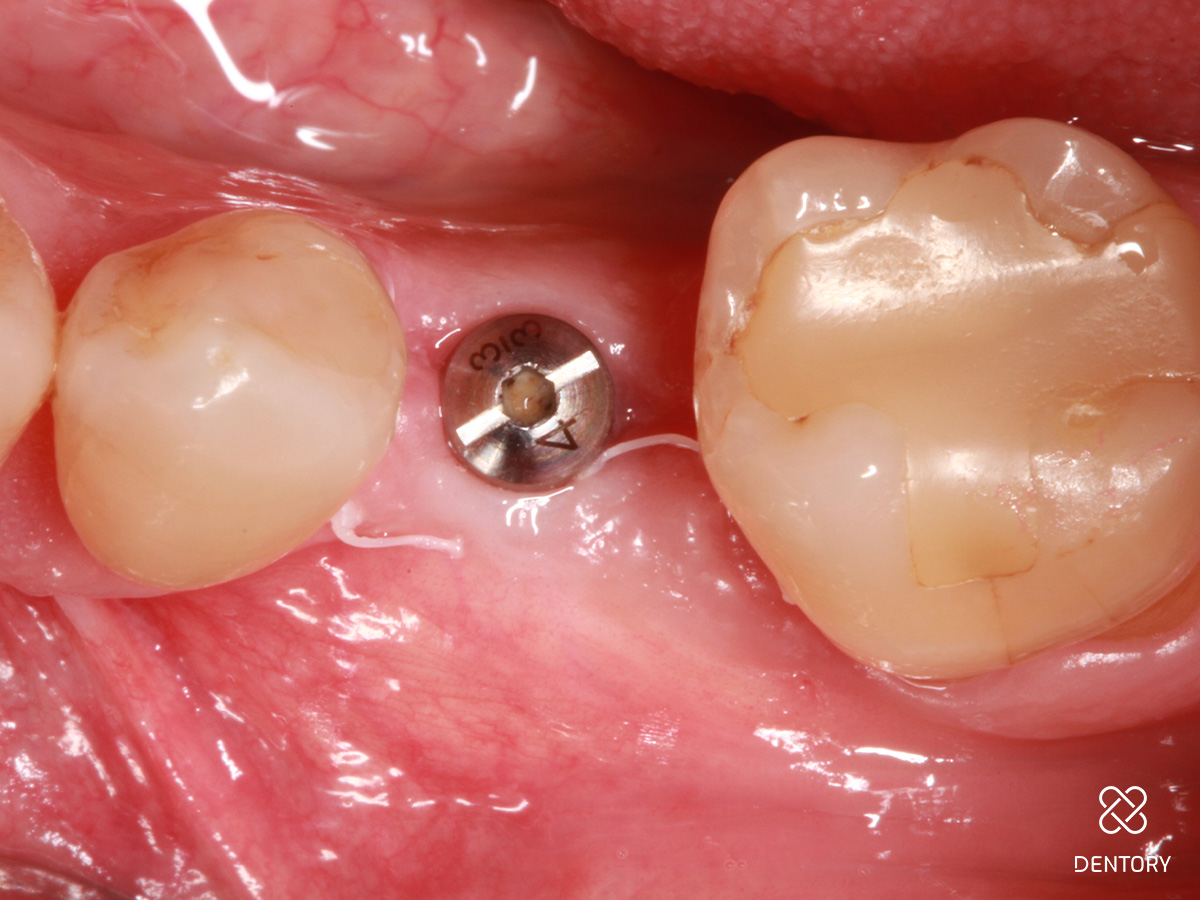

Abbildung 1

Ausgangssituation: Einzelzahnlücke regio 35.